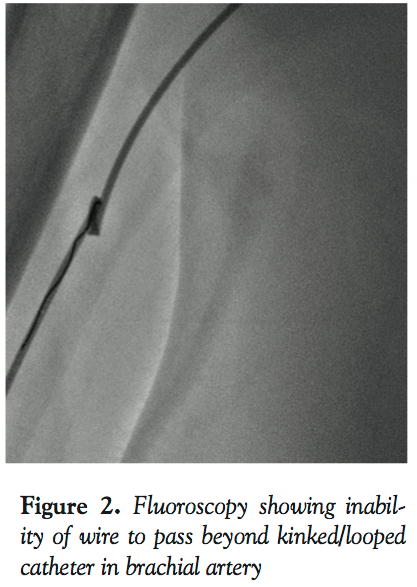

Fr JL4 catheter. Some spasm was encountered going up with the JL4. While clocking and advancing the catheter, we noticed damping of the arterial wave paralleled with inability to further manipulate the catheter. On fluoroscopy, the JL was found looped and kinked on itself in the brachial segment (Figure 1). Different maneuvers to de-loop it failed, including external fixation of the distal part of the catheter at the arm level both by putting circumferential pressure on the arm with our hands as well as by inflating the blood pressure cuff to a different level at the arm so it forms an anchor for us to untwist the loop. We could not even advance a coronary wire into that loop (Figure 2). Another cocktail was used in vain. To resolve our problem, we used the scalpel to cut the proximal part of the JL catheter. Next, we exchanged the 6 Fr 12 cm sheath with a 5 Fr long sheath while the severed and trapped JL4 catheter served as a guidewire. We advanced the sheath up to the anticubital fossa (Figure 3). Under fluoroscopy, we gently pulled the trapped catheter. It smoothly unfolded its loop while slipping into the long sheath, hence freeing the catheter. It is important to mention here that complete inability of the catheter to move due to kink/loop can be a limitation of this technique. Dye was then injected in the catheterless sheath to confirm patency of the brachial artery. We had contemplated using a larger French sheath in lieu of the 5 Fr one based on the fact that the loop has a better chance of slipping into the wider lumen of the larger sheath. The problem was that the introducer of the 6, 7, or 8 Fr sheaths would not go over the 5 Fr catheter, which was thicker than the wire. Also, it would have been incautious to push any of these sheaths without their respective introducer directly over the trapped catheter, which would, at the least, risk stripping the arterial intima. Because of the resulting spasm in the radial artery, the procedure was switched to femoral. Three months later, the patient still has his radial and ulnar pulses in his right hand and no long-term complications were noted. To our knowledge, this is the first description of this method in removing the looped cardiac catheter from the radial access.